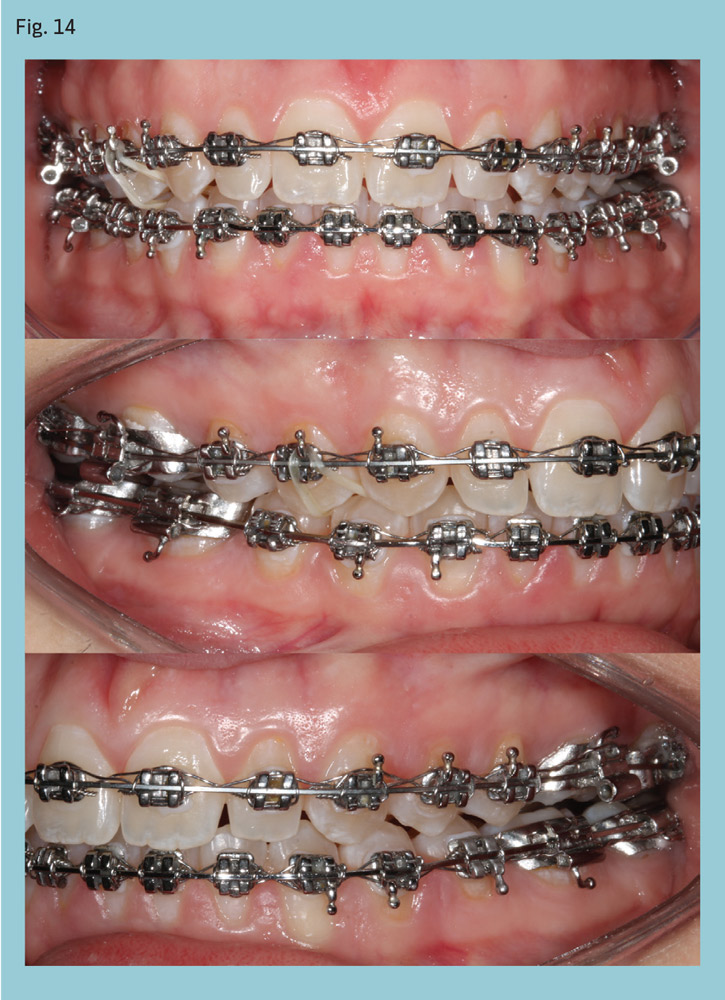

A 20-year-old woman presented with a Class II, Division 2, subdivision malocclusion with mild maxillary crowding (Fig. 11). Her overbite was almost 100 percent and lower midline was deviated to the left. Her condition was compounded by a left posterior crossbite. Cephalometric analysis revealed a dolichofacial pattern and mandibular retrognathia.

After four months of leveling and alignment, PowerScope was placed (Figs. 12-13). The Class II was corrected in three months (Fig. 14) and PowerScope removed. After another three months for coordinating the arches and detailing the occlusion, fixed appliances were debonded, completing 10 months of active treatment (Fig. 15).